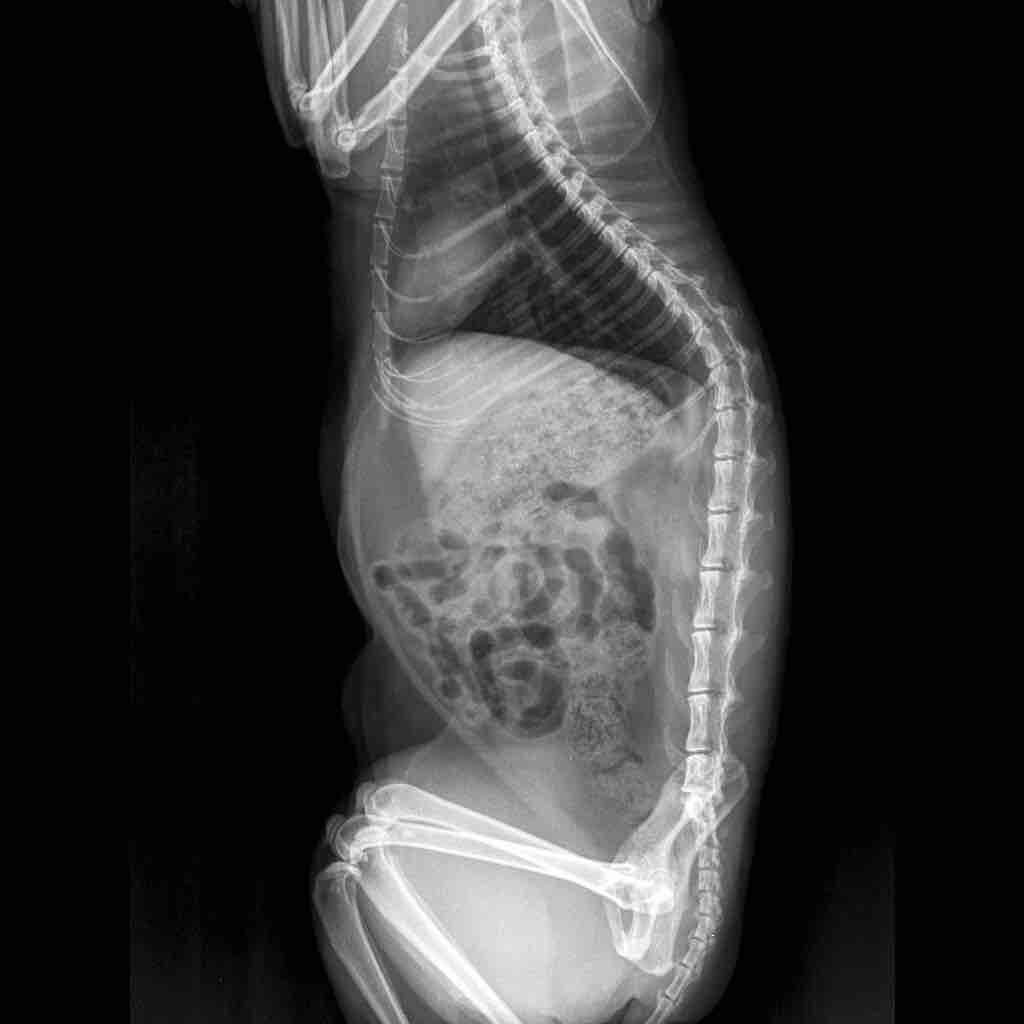

Took biscuit to the vet today and after taking an x-ray we found out that her bladder was full and that there are stones in the bladder. The vet isn’t very optimistic as he said a surgery would only be a temporary solution and that it’s the tendency of her body to create these stones, also there might be complications during the surgery. I have come to you for a second opinion. Please help me.